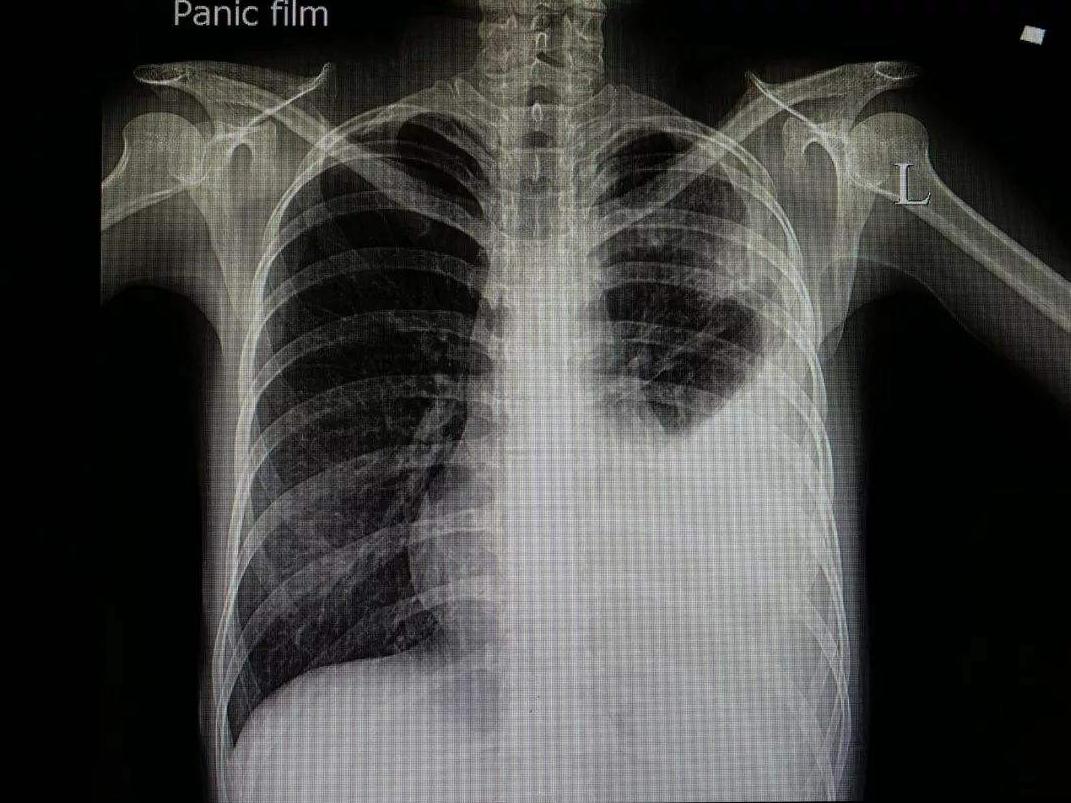

3.1.胸部X线检查

少量积液时肋膈角变钝;中等量积液,肺野中下部呈均匀致密影,呈上缘外高内低的凹陷影;大量积液患侧全呈致密影,纵隔向健侧移位。肺下积液出现膈升高假象,侧卧位或水平卧位投照可确定。叶间包裹积液时在胸膜腔或叶间不同部位,有近似圆形、椭圆形的阴影,侧位片可确定部位。